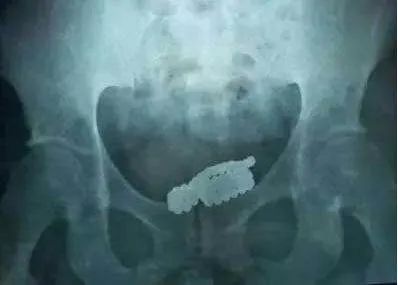

术中切开脓肿充分引流

在探查阴囊过程中

柯井卫主治医师在

尿道下方触摸到一个

“马克笔”大小硬物

继续探查又发现了

3根形状各异的管状物

柯井卫主治医师小心翼翼

一一将异物取出

“马克笔”硬物

足足有10厘米长,2厘米粗

是黄色管状物上面覆有结石形成的

另外三根则是形状各异的管状物